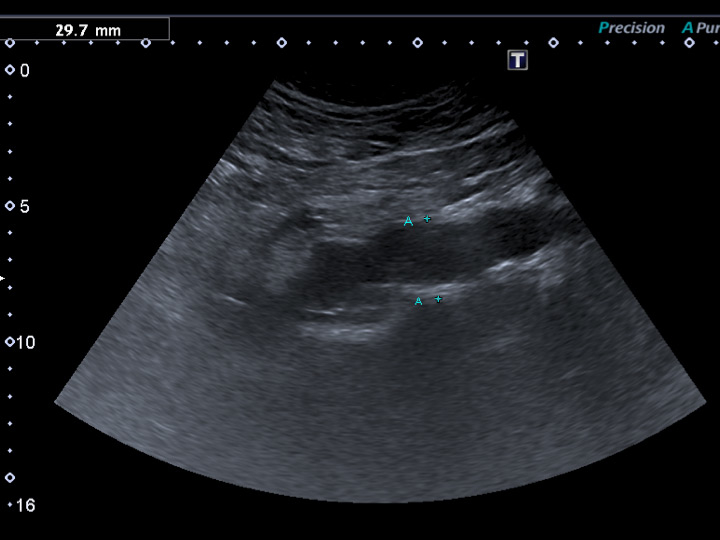

Figure 1

Previously undiagnosed small abdominal aortic aneurysm detected on vascular duplex ultrasound in a 62-year-old smoker with erectile dysfunction, otherwise asymptomatic regarding cardiovascular disease.

Arterial workup of ED patients with cardiovascular risk factors primarily consists of a noninvasive haemodynamic workup such as oscillometry and assessment of ankle-brachial index. In addition, duplex-sonographic workup of erection-related arteries (i.e. abdominal aorta, common and internal iliac arteries) is warranted. Given the association of vascular ED with the potential presence of peripheral arterial disease, duplex-sonographic evaluation of the femoropopliteal and carotid arteries may be considered.

Figure 1 shows a sonographic depiction of a previously undiagnosed abdominal aortic aneurysm in an otherwise healthy and asymptomatic smoker referred for vascular workup of erectile dysfunction.